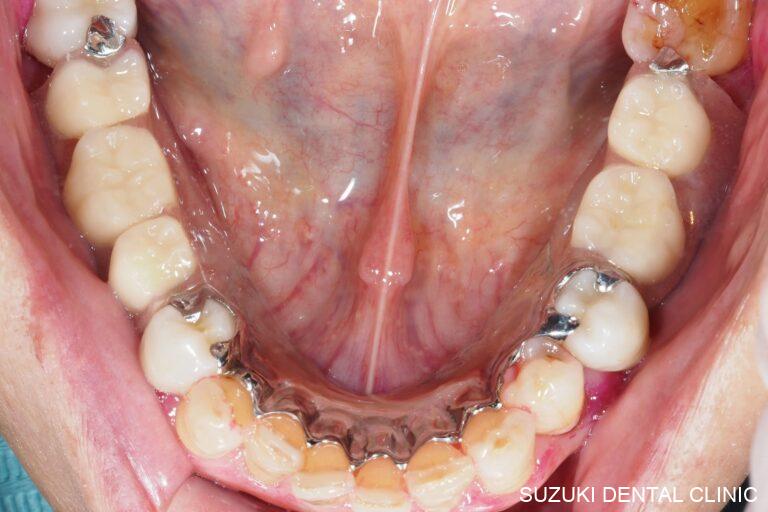

これまでの臨床経験による技術と、咬合理論を駆使して、機能と審美性を兼ね備えた美しい口元と快適な食生活を取り戻すことは、患者のQOLを高めると共に我々の存在意義を同時に揺るぎないものとすることと確信しています。